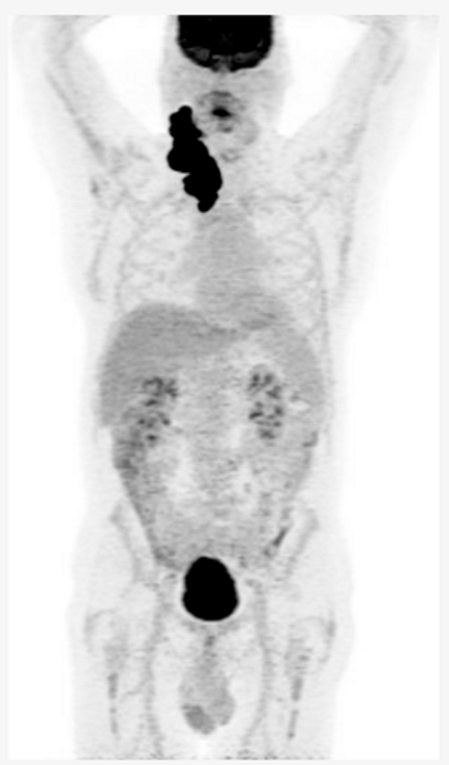

Key Clinical Features â˘â46-year-old indigenous male from a remote area of northern Canada â˘âComorbidities: HTN, CAD, osteoarthritis â˘âPresented with a large neck mass â˘âStage IV, IPI 4/5, ECOG PS 2 Diagnosis â˘âSent to a treatment center 2,000 km away for cervical node core biopsy, non-diagnostic â˘âSent back again for excisional biopsy, interval between biopsies was 2 months â˘âDLBCL, non-GCB, double expressor, no MYC rearrangement Initial Treatment â˘âPlan for R-CHOP x 6 but patient did not show for 1st cycle â˘âTreatment start was delayed 6-weeks and patient elected to return home between cycles â˘âPET scan after 3 cycles demonstrates mixed response Second-line Treatment â˘âPlan for ASCT and discussed salvage with R-ICE versus R-GDP â˘âChose R-ICE to get longer time at home between treatment â˘âProgression after 2 cycles Third-line Treatment â˘âDiscussion of CAR-T cell therapy versus BsAb therapy, patient elected to proceed with BsAb therapy |